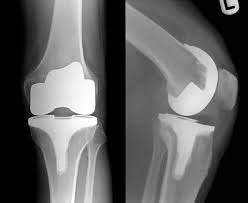

I have gotten a bunch of messages from other Crossfitters, who have bad knees, who have asked about working out with a knee replacement, what made me get the knee replacement, how my knee feels now, etc....

Truthfully, I got the first knee replacement because I couldn't do most crossfit workouts without modifying or without pain and, just walking across the street had become a bit of a chore. I probably could have gone on with my life, limping and just riding the exercise bike, and warded off a replacement for quite a few years. At that time in my life though, that wasn't an option. I was willing to take any measure to try to get back into the "game". (Being able to walk without pain was a bonus)

These days, my left knee is starting to hurt and I have started to wrap my head around getting my second knee replaced. It won't happen though until it is an absolute necessity. Walking will have to be a chore, crossfit impossible and working difficult. Then, I will have the surgery.  Since I know what to expect now, it will be a well thought out decision. I am very happy with the results from the first surgery but, it is a long and tedious recovery. One I am not in a hurry to repeat if I don't have to.